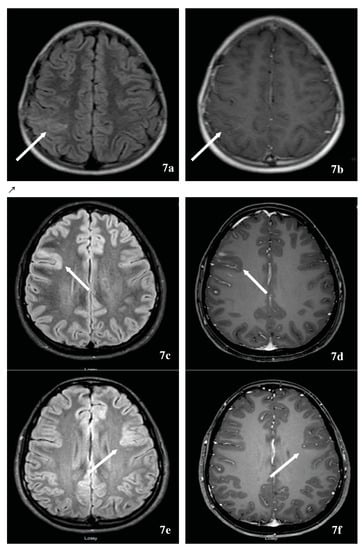

7.1. Multiple Sclerosis-Associated Tumefactive Demyelinating Lesions (MS-TDLs)

7.2. Neuromyelitis Optica Spectrum Disorder-Associated Tumefactive Demyelinating Lesions (NMOSD-TDL) and Hemispheric Presentations

7.3. The relationship of Balo’s Concentric Sclerosis to TDL, MS and NMOSD